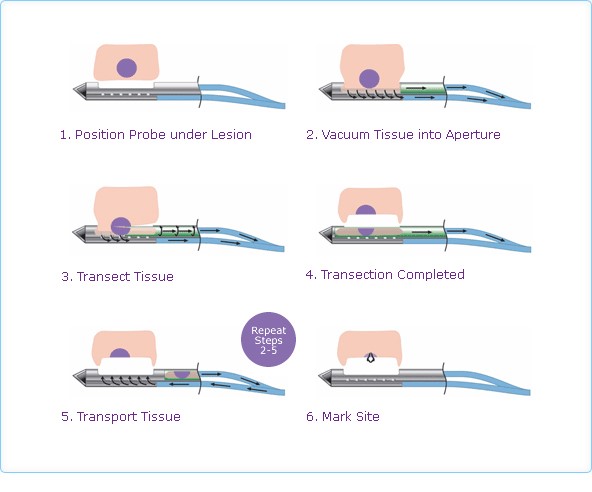

1. Định vị Kim dưới tổn thương, 2. Hút mô vào trong máng, 3. Cắt khối u,

4. Di chuyển phần mô được cắt ra ngoài bầu đựng, 5. Lặp lại bước 2, 3, 4 cho tới khi hết lấy hết toàn bộ tổn thương